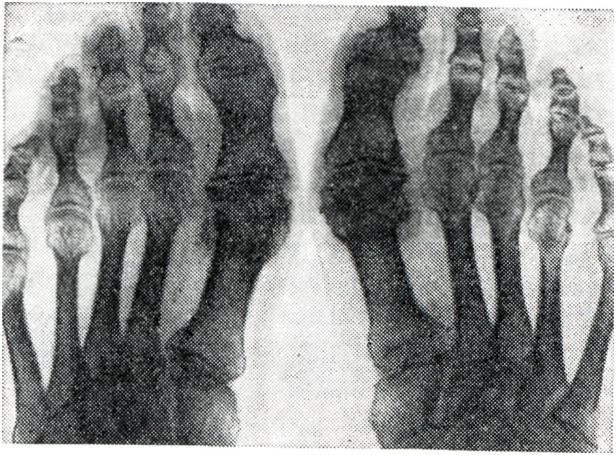

Рис. 10.

Рентгенограмма кисти больного с геберденовскими узелками в области II—V дистальных межфаланговых суставов.

Геберденовские (в дистальных межфаланговых суставах) и бушаровские (в проксимальных межфаланговых суставах) узелки кистей рук.

Артроз дистальных межфаланговых суставов пальцев рук (геберденовские узелки, геберденоартроз) представляет собой одну из наиболее частых локализаций первичного артроза, обычно поражает женщин, особенно в климактерическом и постклимактерическом периодах. Геберденовские узелки (рис. 9, 10) считаются ранним проявлением первичного генетически обусловленного полиартроза, который одновременно связывают с перегрузкой дистальных межфаланговых суставов мелкой и напряженной работой. Геберденовские узелки развиваются очень медленно, бессимптомно, часто незаметно для самого больного. Лишь в поздние сроки появляются небольшие боли, обычно при смене погоды, небольшая болезненность при пальпации и образуются заметные возвышения по обеим сторонам тыльной поверхности дистальных межфаланговых суставов. На рентгенограмме отмечается сужение суставных щелей, неровность суставных поверхностей, подхрящевой склероз и боковые остеофиты. Артроз проксимальных межфаланговых суставов пальцев рук (бушаровские узелки) встречается значительно реже, чем геберденовские узелки, но по своей клинической и рентгенологической картине от последних почти не отличается. Как правило, бушаровские узелки появляются у лиц, имеющих геберденовские узелки (рис. 9). Это помогает отличить их от ревматоидного артрита, при котором очень часто поражаются проксимальные межфаланговые и пястно-фаланговые суставы раздельно или совместно. Кроме того, деформация сустава при бушаровских узелках обусловлена не утолщением мягких тканей (как при артритах), а твердыми костными разрастаниями.